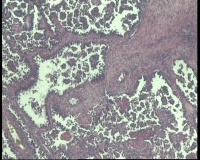

| 性别 | 女 | 年龄 | 53岁 | 临床诊断 | 右侧卵巢囊肿 |

| 一般病史 | 彩超:盆腔可见囊实性回声,囊性为主,大小约5.0x3.7厘米,其内可见分隔回声,部分分隔内回声不纯净,形态欠规整 | ||||

| 标本名称 | 腔镜下右侧卵巢囊肿手术 | ||||

| 大体所见 | 囊壁样组织5.5x5.0厘米,4.5x2.5厘米2块,壁厚0.1-0.2lm,囊壁大部分光滑,局灶见0.7x0.5x0.3厘米淡黄色突起组织,另见淡黄色、肉粉色质软组织2.8厘米一堆。 | ||||